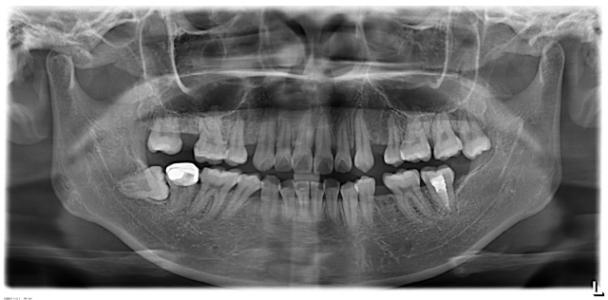

全景片上牙根平行度还不错,患者右下的骨岛可以看出下颌是中度支抗